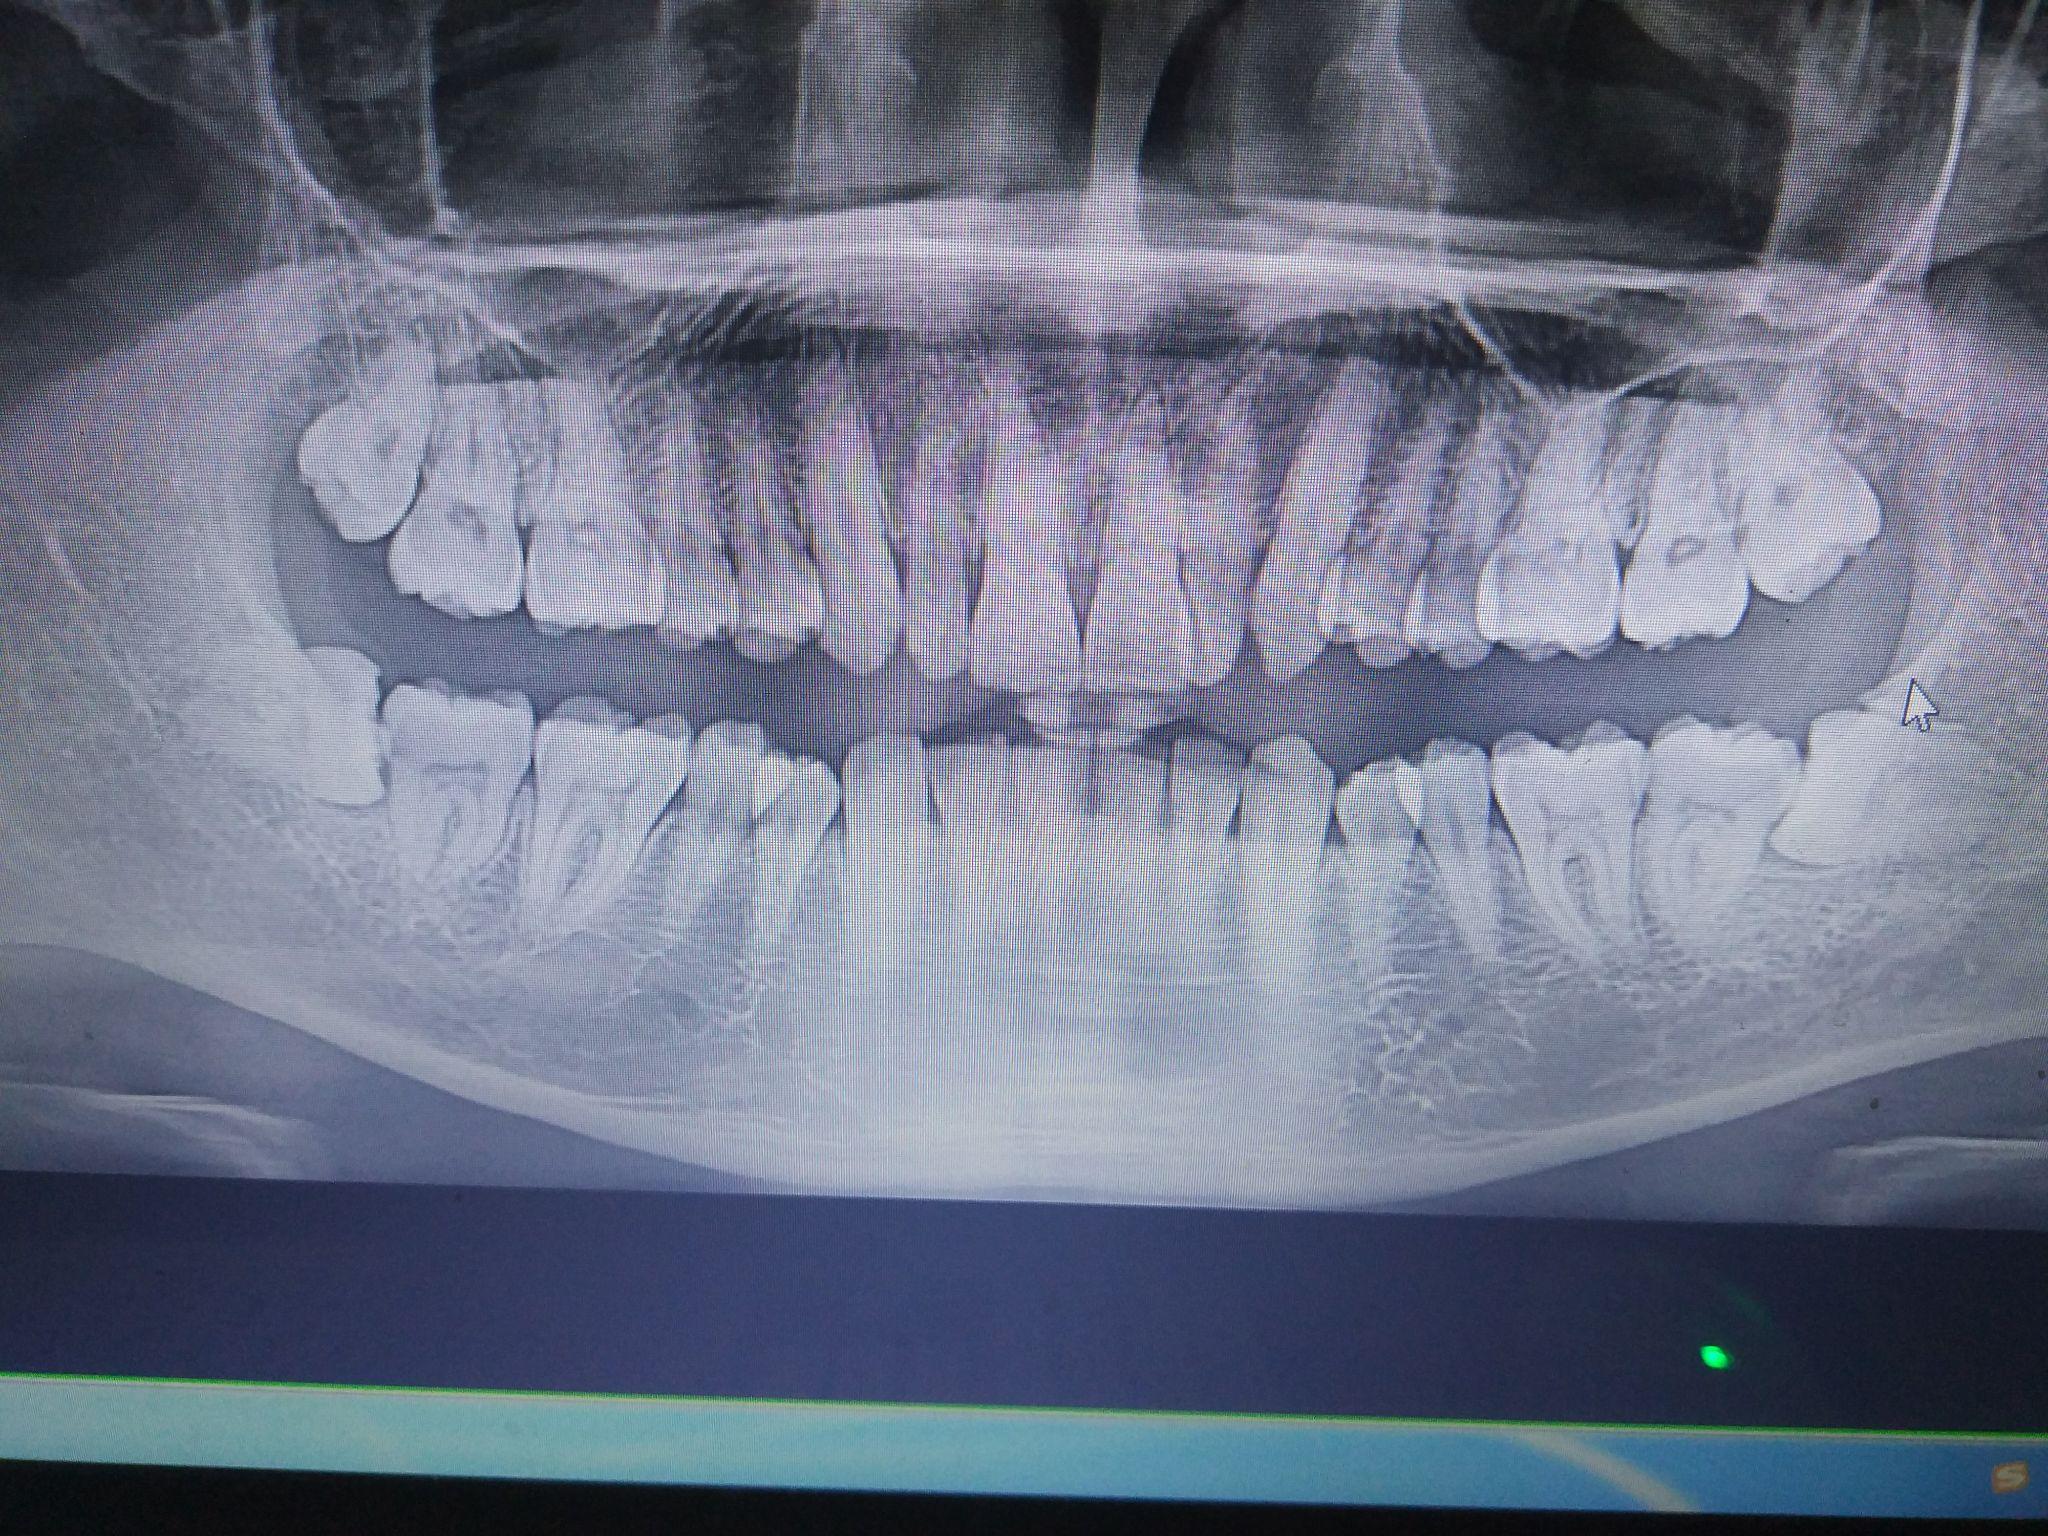

今儿去拍了牙片,有两颗阻生智齿,想问问大家,我这种难度大吗?

图片尺寸2048x1536